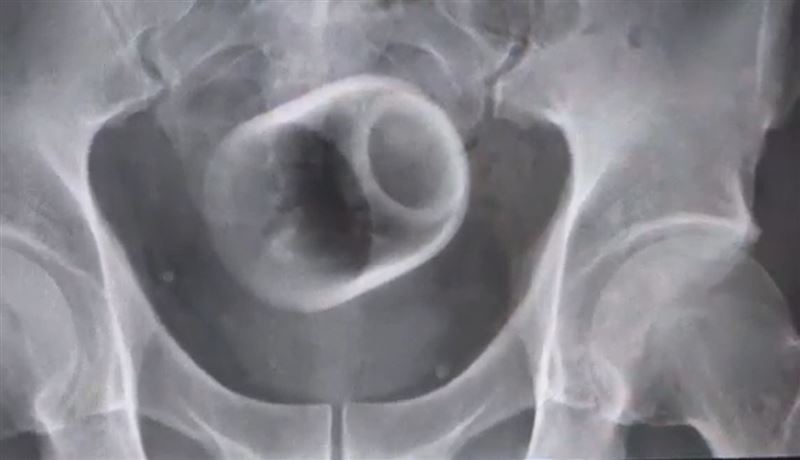

一名中年男子因3天無法解便,腹痛求診,照X光才發現腸子被塞進一個茶杯,緊急開刀取出。(圖/大甲李綜合醫院提供)

一名中年男子因腹脹連三天無法排便,肚子痛到無法忍受,趕緊到醫院求診,經過X光檢查,醫師驚見患者的肛門竟然塞一個直徑約6公分、高8公分的「陶瓷杯」!外科醫師原本使用器械將杯子夾出來,但杯緣光滑無法施力,加上堵塞時間長,杯子全被大腸包住,部分腸子已缺血壞死,最後只好全身麻醉「開腸破肚」才把男子體內的杯子順利取出。

直徑約6公分、高約8公分的陶瓷杯被腸子包住,因杯緣光滑難以夾出,最後只好開刀將杯子順利取出。(圖/大甲李綜合醫院提供)

駐診李綜合醫院的台中榮總外科醫師吳坤達表示,該名患者到院時,自訴三天無法排便非常困擾,因害羞未提及自己肛門塞了一個杯子,經過X光攝影,發現患者骨盆腔內竟有「杯子」形狀的異物,醫師當場嚇一大跳,立即安排進手術室,將杯子取出。

醫師表示,一開始試著用器械把夾出來,但杯子外表光滑,用了很多器械,試了很多次都無法成功,後來再使用腹腔鏡,依舊無法順利取出,擔心把杯子夾碎,傷及患者甚至造成感染風險,最後只好剖腹,直接把腸子劃開,耗費2個多小時才順利取出杯子,同時做了一個人工造口,讓患者能夠暫時解便。